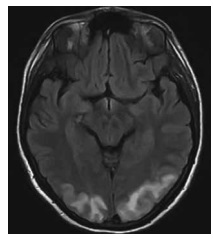

Ainda com base na situação hipotética apresentada, e na imagem da ressonância magnética de crânio acima, assinale a alternativa correta.